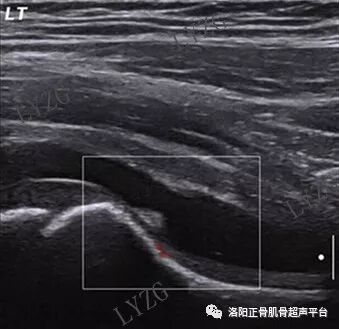

双侧对比,右髋关节前隐窝内未见大于2mm积液,左髋关节前隐窝内积液并可见丝带状滑膜增生

左髋关节前隐窝内及股骨头前方关节腔内均可见积液并可见少量团块状滑膜增生